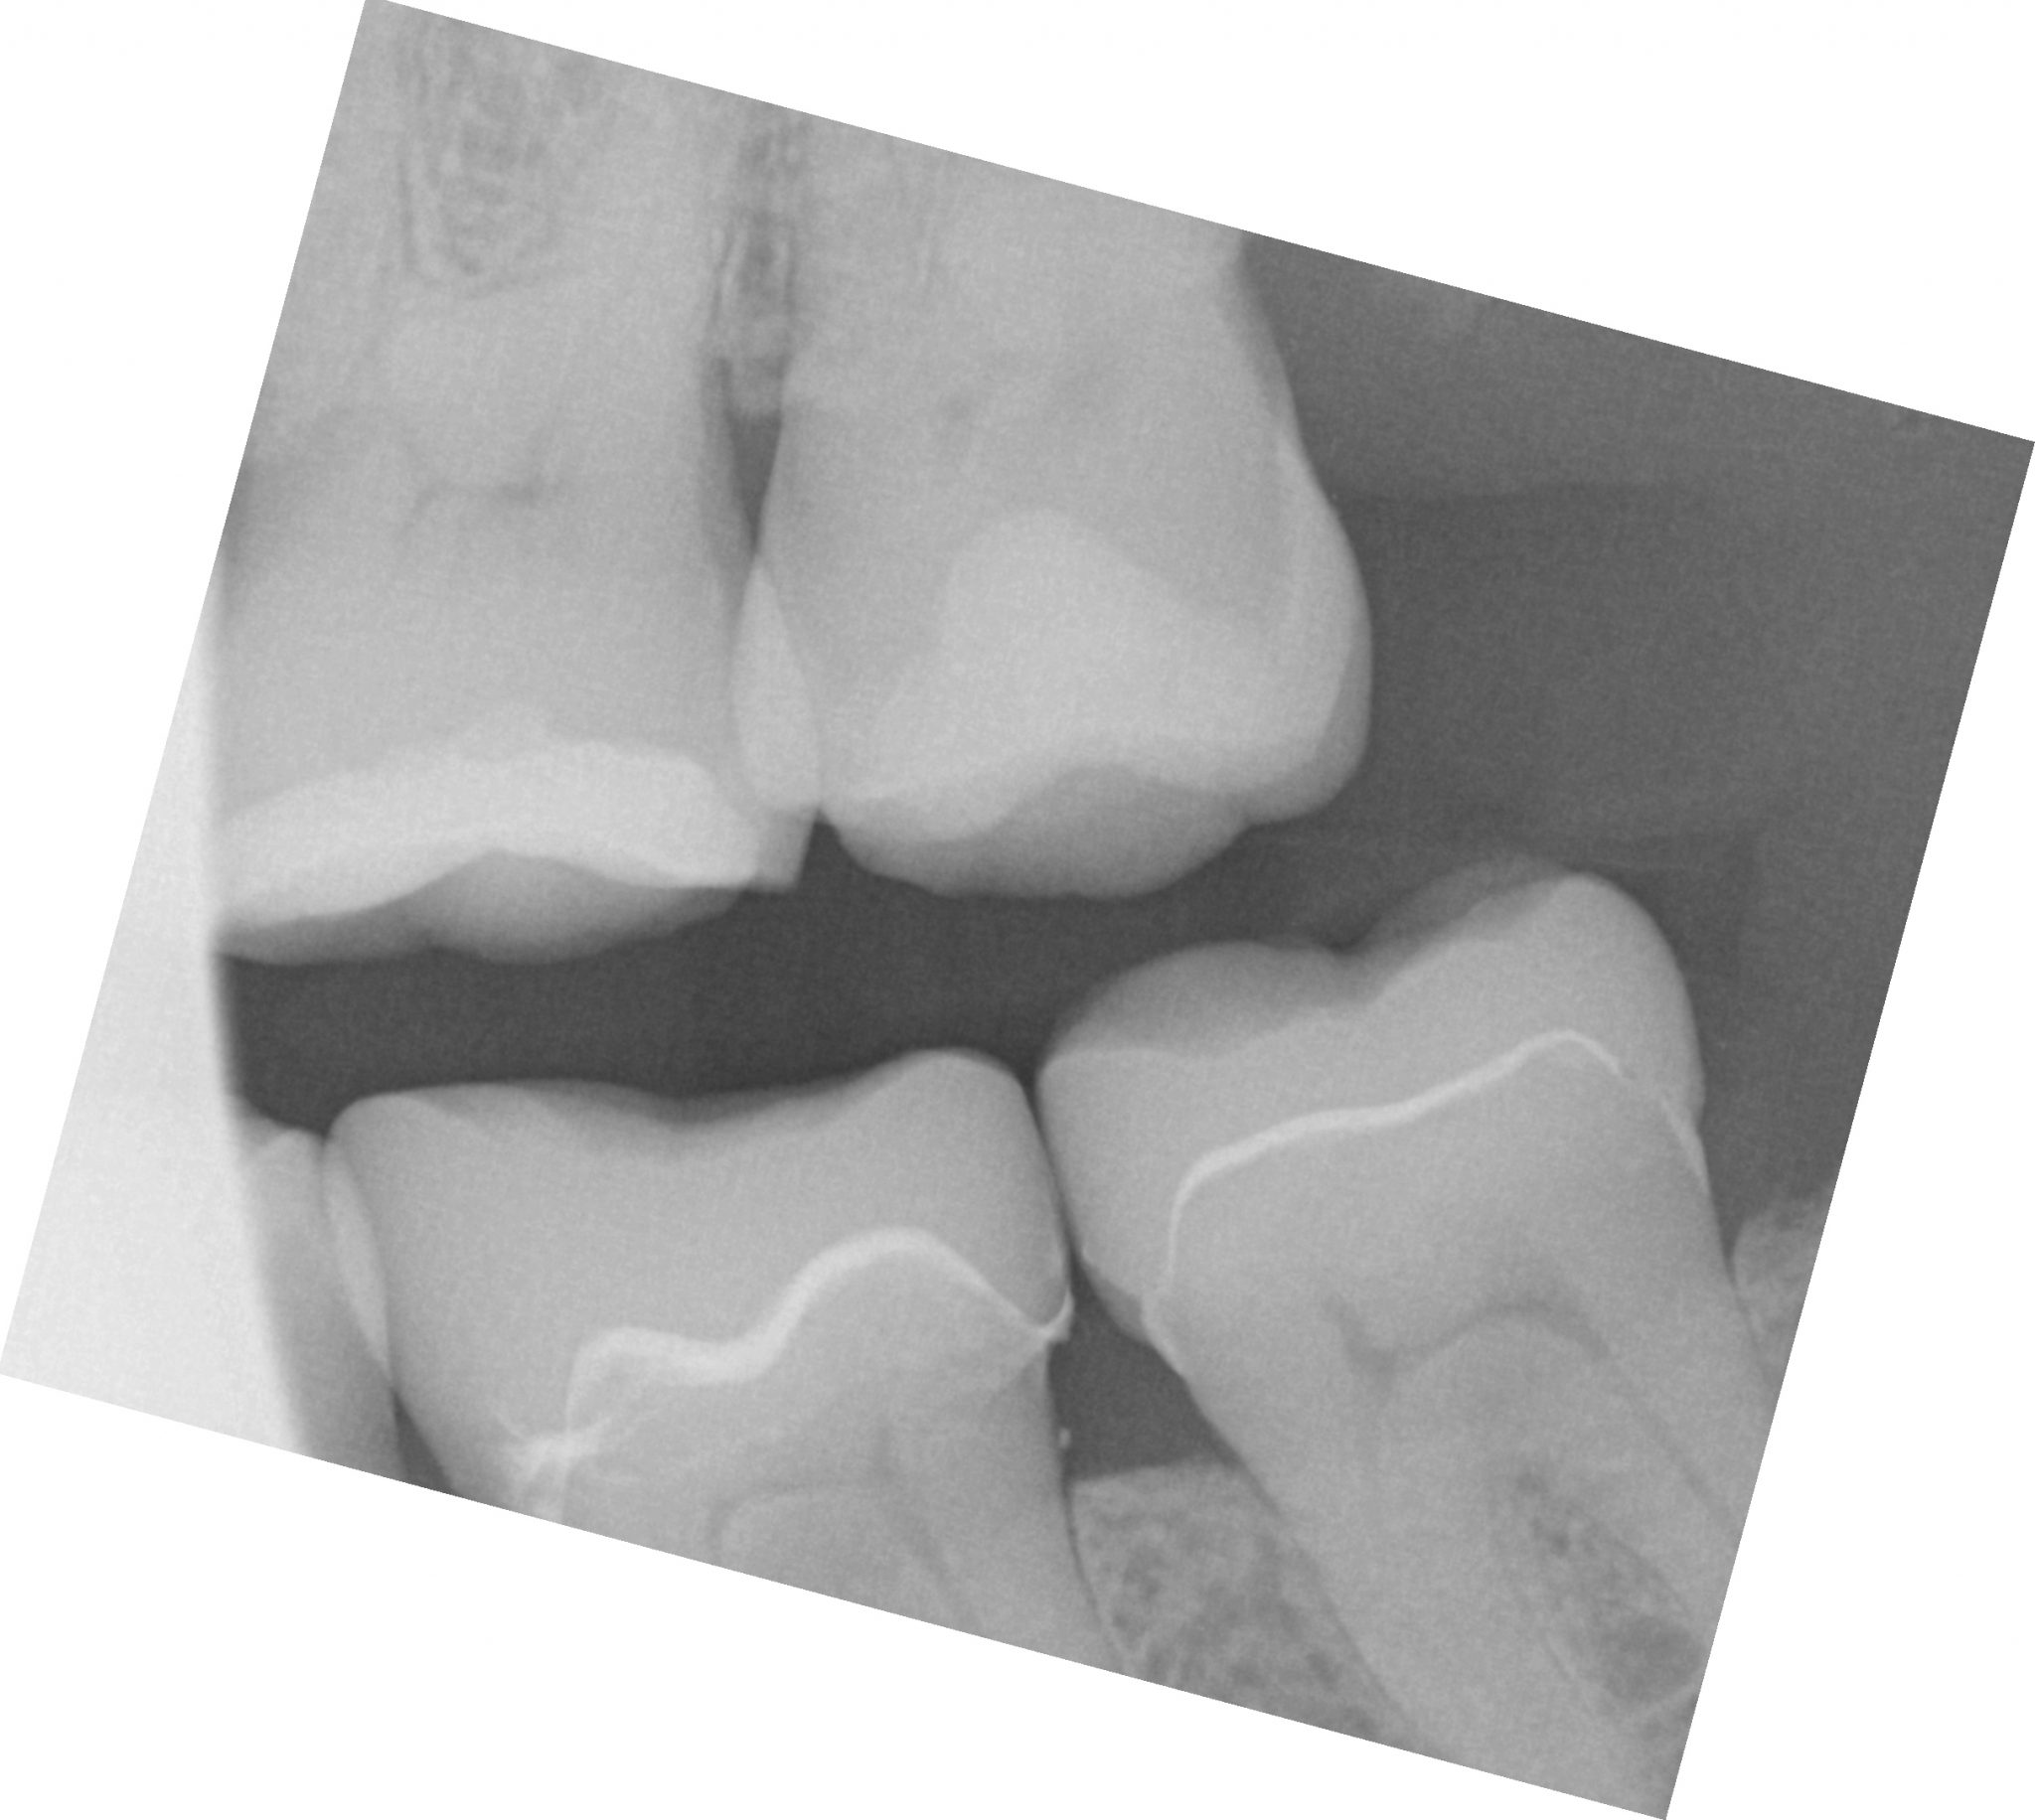

While the second molar is being designed and milled in the first case, we will launch a second window by cloning the first case. All the data remains the same and this time we crop out the first molar digitally and protect the rest of the arch. Once the first molar is isolated, it is digitally captured and then designed and milled.

To manage the contact between the two crowns, there are many advanced applications. Here is a simple explanation of how we use the prep model from case 1 as the pre-op model for case two. Since the second molar in case 1 made contact with the distal wall of the first molar, when we design the crown for the first molar in case 2, all we have to do is make sure the distal wall is flush to the pre-op. This guarantees us a contact between the two. There are lots of shortcuts to this puzzle once you get the basics of digital impressions under your belt.